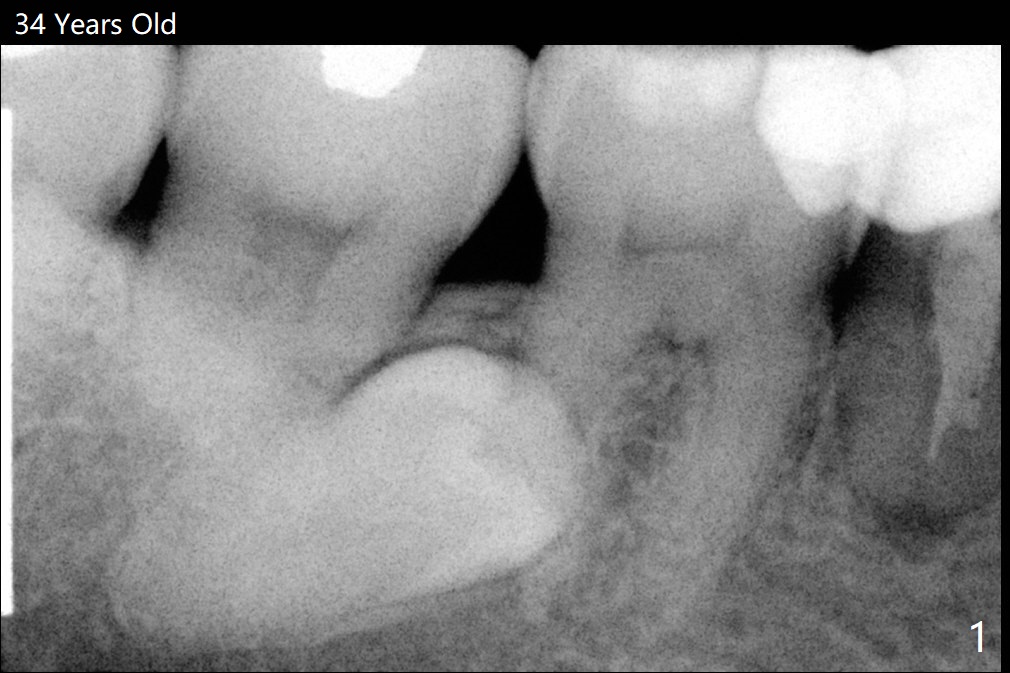

A 34-year-old woman has 2 supernumerary lower 2nd premolars located between the 1st and 2nd molars (Fig.1,2). Ten years later, the lower left 2nd molar has mobility associated with root resorption (Fig.3).